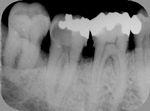

◆根管治療

むし歯等で歯の神経が死んでしまった場合に必要となる根の治療です。

根管治療X線写真